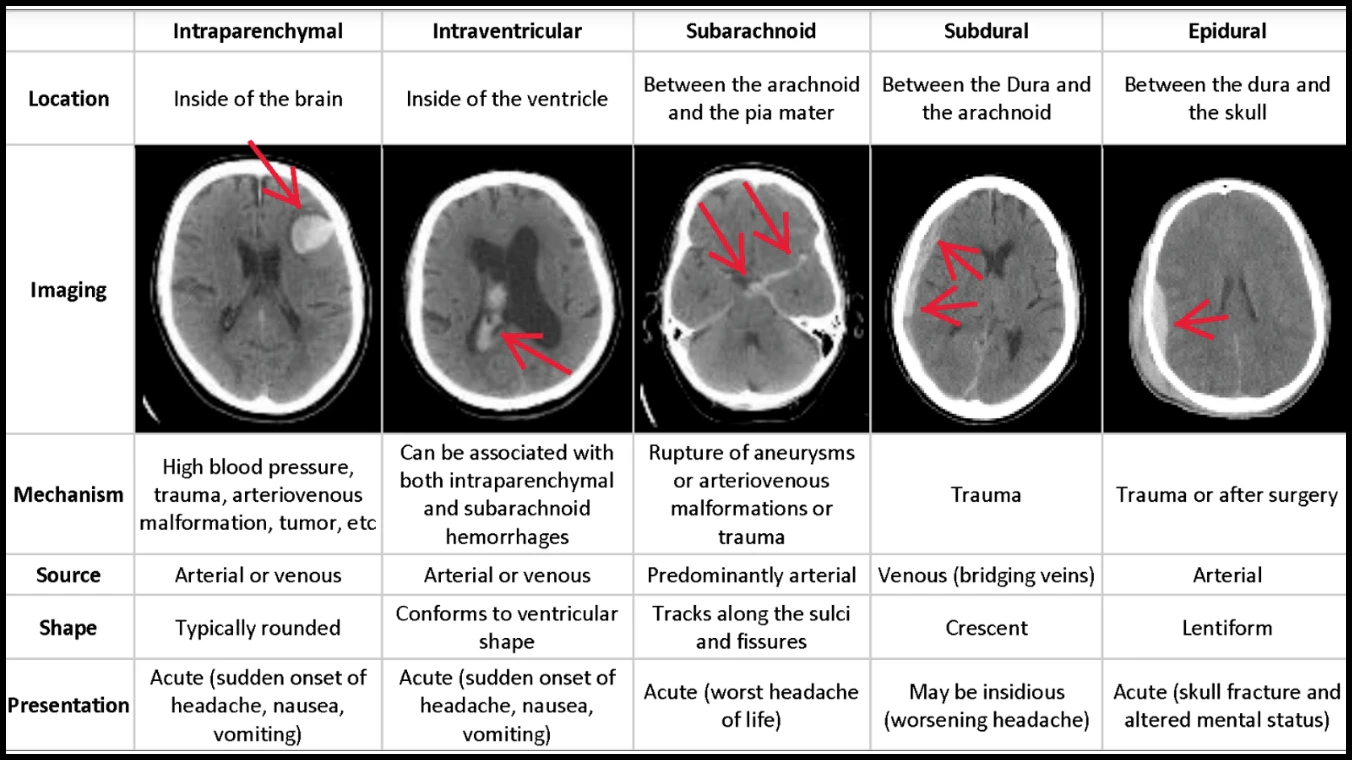

転移学習を用いた頭蓋内出血の画像判定モデル作成(Python)

転移学習を用いた頭蓋内出血の画像判定モデル作成

(Python)